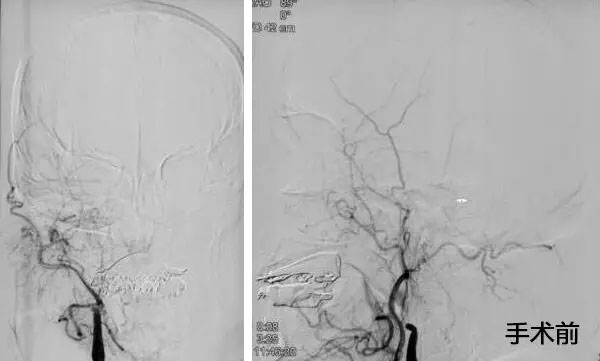

▲ 患者取栓前后DSA造影圖

10:00am,患者被送入手術(shù)室,全麻下行全腦血管造影示:右側(cè)頸內(nèi)動脈處血流完全閉塞,血栓位于右側(cè)頸內(nèi)動脈T型分叉部,其他血管代償不好,必須及時取栓干預。將微導管、微導絲送達血栓遠瑞,微導管、微導絲到位后,成功釋放支架,多次抽吸+支架拉栓,歷時三個小時,取出大量血栓,患者血管達到2B級開通,血管恢復了供血。術(shù)后,轉(zhuǎn)入九樓ICU。目前患者狀態(tài)平穩(wěn),正在康復中。